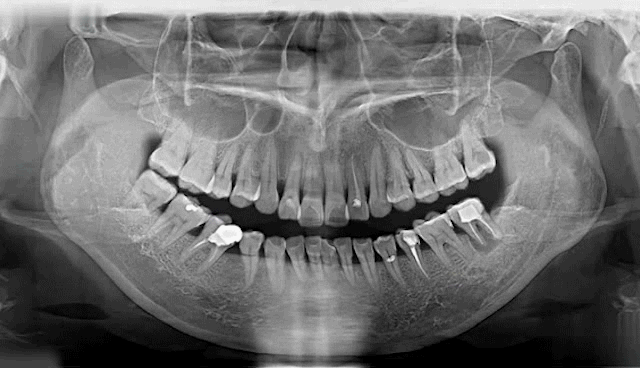

中华医学会调查结果显示:我国45岁以上中老年人79%存在缺牙现象,超过90%以上公民有牙齿不齐、龋齿、牙周病口腔问题,其中12岁儿童的恒牙患龋概率达到29%,牙颌畸形发病率恒牙期为72.92%,70岁以上的老年人许多都处在缺牙甚至无牙状态。

牙齿缺失会引起邻牙松动、对牙伸长、引发牙周病,最终牙齿脱落等一系列问题,还会因咬合紊乱致使面容苍老、咀嚼功能变差引发肠胃疾病,甚至影响身体健康。

种植牙是医学界公认的理想修复方式,被誉为“人类的第三副牙”。相比活动假牙不舒服、难清洗、容易引起口腔黏膜病变,种植牙更稳固耐用,舒适美观,咀嚼功能好,一次种植,终生受用。种植牙不仅是中老年人的专利,年轻人因意外、牙病等造成牙齿缺失,也能够通过种植牙进行修复治疗,重获美丽笑容。